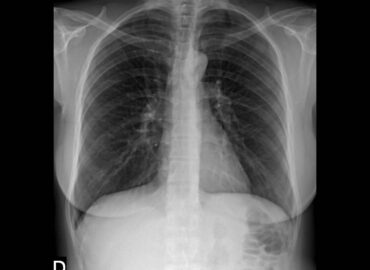

Mujer de 46 años con tos de larga data. Presenta como antecedentes: Enfermedad de Hashimoto medicada levotiroxina 88 mg/d […]